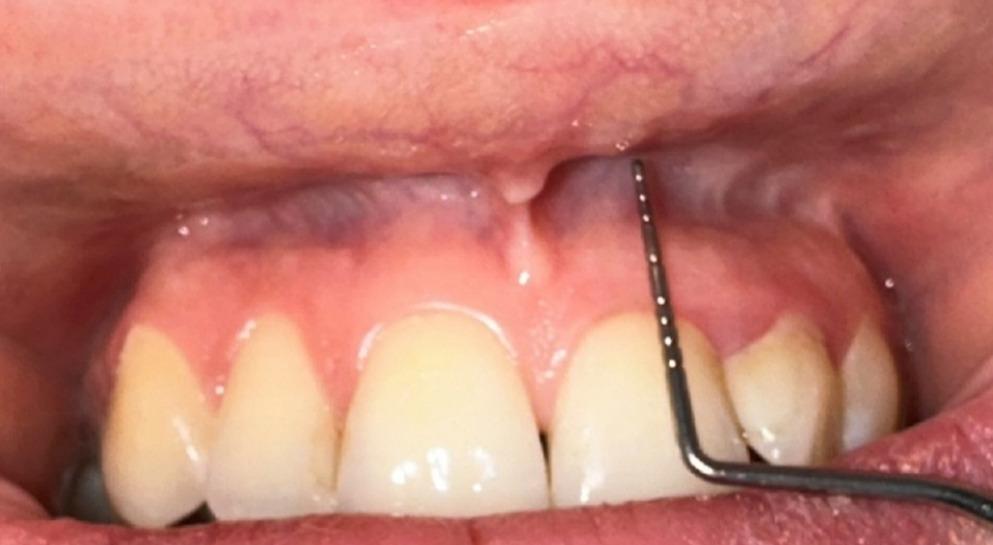

• VD: Defined as the distance between the coronal border of the attached gingiva and the deepest point of the mucobuccal fold (Fig. 1) [13]. Measurements were taken at the mid-buccal point of each implant; the lip/cheek was gently retracted to reveal the mucobuccal fold, taking care not to artificially increase the anatomical depth by stretching the tissue [13]. VD was recorded in millimeters and evaluated as both a continuous variable and a categorical variable in the analyses. In categorical classification, implants were grouped as shallow VD (≤ 4 mm) and adequate VD (> 4 mm) [13, 25, 26]. The four-millimeter threshold value was determined by considering the basic approaches used in the literature [13, 25] and the fact that the finding retained its significance in threshold sensitivity analyses conducted in the 2–6 mm range.

Fig. 1

Measurement of vestibular depth